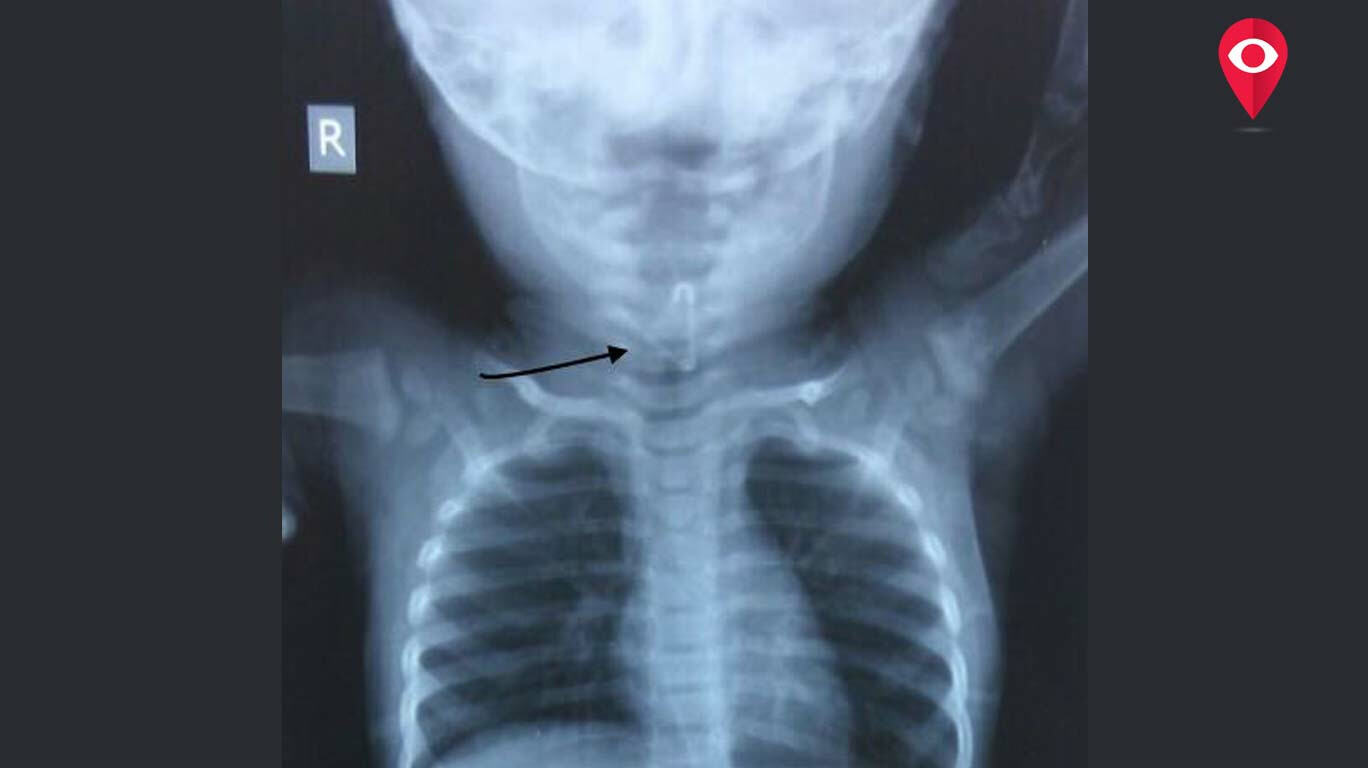

What If We Swallow Staple Pin. It becomes coated as it is passed. But some objects can get. Once the staple is in the stomach, it should pass uneventfully. The objects posing the greatest risks include sharp objects, broken glass, batteries, and magnets. Symptoms include chest pain, coughing, gagging, difficulty breathing, vomiting, and abdominal pain. if you have swallowed a stapler pin (that means it has gone into your stomach and not stuck in your food pipe) then you should forget it. 2 doctors weighed in across 2 answers. my one year old may have swallowed a piece of a flooring staple, what should i do? young children, and sometimes older children and adults, may swallow toys, coins, safety pins, buttons, bones, wood,. a swallowed foreign object is one that is not supposed to be in the gastrointestinal tract. if you swallow a foreign object, it usually will pass through your system without notice. if you swallow a staple and experience any pain, difficulty swallowing, vomiting, fever, or blood in your stool, you should seek medical. Generally it is more likely than not that sharp objects will be pass through the intestine.